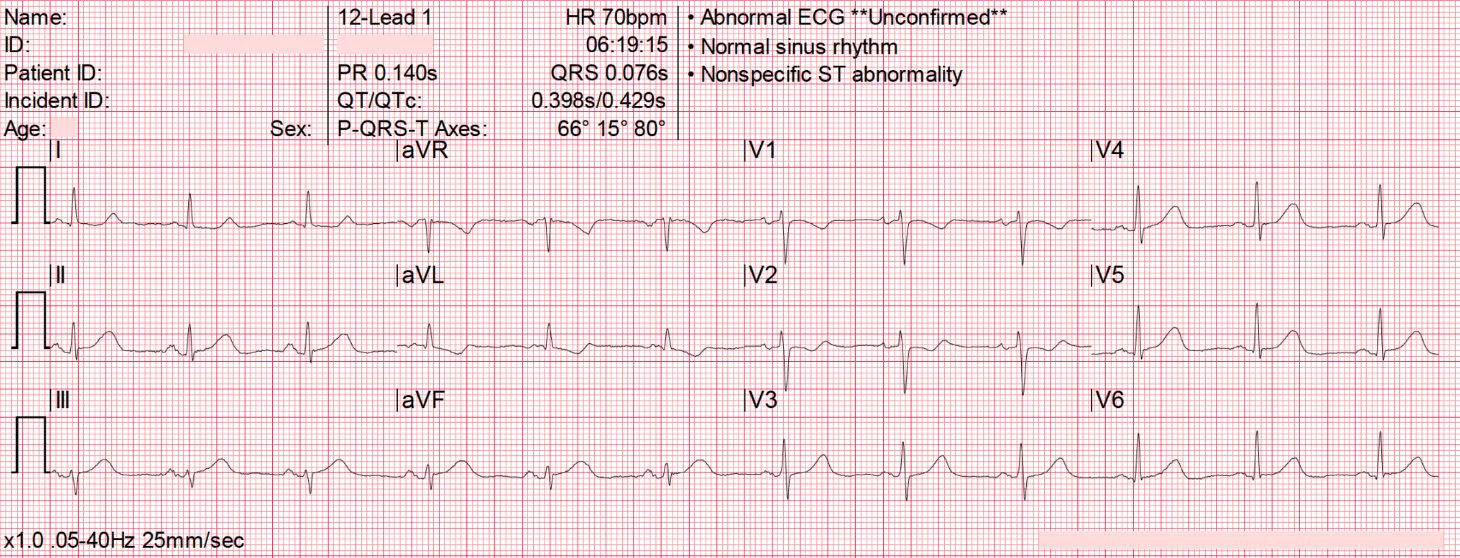

- EKG: 47yoM coming in with cc of nausea

- https://litfl.com/ecg-case-035/

- T waves in leads III and aVF appear to tower over the preceding QRS complex, and have a wide, “bulky” appearance. Such changes are consistent with hyperacute T waves (HATW) representative of hyperacute occlusion and evolving ST elevation

- There is reciprocal ST depression in V1-3 and I

- These changes are suggestive of hyperacute inferior OMI, likely due to occlusion of a dominant RCA given the lack of ST elevation seen in lateral leads. This ECG was faxed from the pre-hospital environment — by the time of arrival to an emergency department it is likely that we would see classical ST elevation evolving.